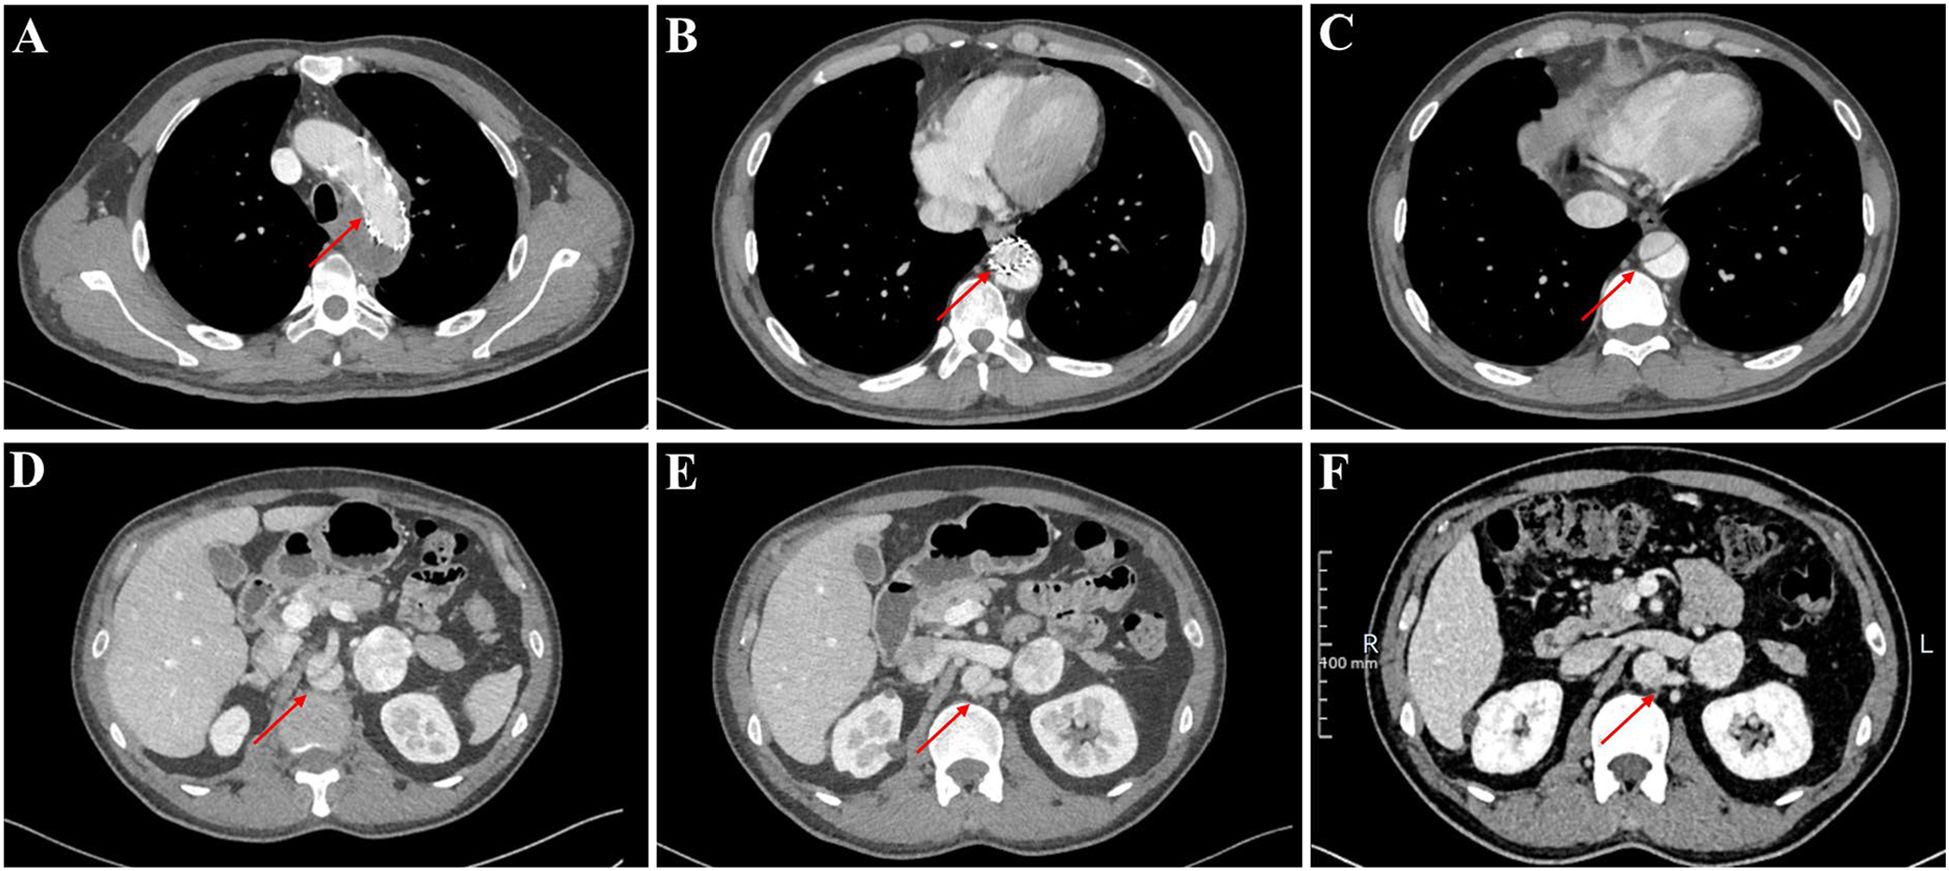

Notably, our evaluation revealed a persistent aortic dissection extending from the distal descending aorta to the abdominal aorta, raising concerns regarding the efficacy of the prior endovascular stent grafting. To elucidate whether this represented disease progression or incomplete exclusion of the false lumen, we conducted a comparative analysis of pre- and post-procedural CT imaging. The dissection morphology and extent demonstrated no significant interval change, indicating failure of the initial endograft to achieve complete sealing. Further scrutiny of the CT angiography identified the left renal artery originating from the false lumen (Figure 4). Therefore, complete endovascular exclusion of the dissection flap would thus risk compromising left renal perfusion, potentially leading to ischemic nephropathy—a therapeutic dilemma corroborated through MDT consultation with the original surgical team.

Figure 4. The thoracoabdominal CT angiography (CTA) findings of the patient. (A–E) Current CTA study performed at our institution. (F) Prior external CTA for comparison.